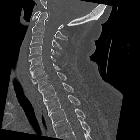

Kissing

carotids: a lovely term for an anatomic variant with great clinical significance. Sagittal reconstructed image showing the retropharyngeal course of the right internal carotid artery (arrowhead).

carotids: a lovely term for an anatomic variant with great clinical significance. Coronal reconstructed image showing the two internal carotid arteries in close proximity (arrowheads).